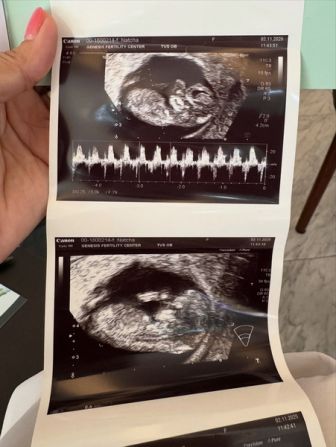

นับถือใจ "ครูก้อย" ภรรยา "เจมส์ เรืองศักดิ์" ตัดสินใจเย็บปากมดลูกขณะตั้งครรภ์ได้ 3 เดือน จากภาวะปากมดลูกสั้น ป้องกันคลอดก่อนกำหนด

เรียกได้ว่าเป็นคุณแม่หัวใจนักวิทยาศาสตร์ที่ทั้งเก่งและแกร่ง สำหรับ “ครูก้อย–นัชชา ลอยชูศักดิ์” ภรรยาของนักร้องดัง “เจมส์ เรืองศักดิ์ ลอยชูศักดิ์” ที่สามารถฝ่าฟันอุปสรรคท้องยากหลายอย่าง กว่าจะมีเบบี๋คนที่ 2 ในวัย 42 ปี โดยครูก้อยได้โพสต์อัปเดทการพักฟื้นหลังจากการเข้ารับการเย็บปากมดลูก ผ่านเฟซบุ๊ก “นัชชา ลอยชูศักดิ์” ขณะตั้งครรภ์ได้เพียง 3 เดือน เนื่องจากมีภาวะปากมดลูกสั้น ซึ่งการรักษาผ่านไปได้ด้วยดี

ทั้งนี้ครูก้อยเคยมีประสบการณ์เข้ารับการเย็บปากมดลูกมาแล้วเมื่อตอนตั้งครรภ์ลูกสาวคนแรก “น้องเมดา อันโดรเมดา” จึงทำให้ครูก้อยไม่ลังเลในการเข้ารับการเย็บปากมดลูกในครั้งนี้ โดยครูก้อยไม่รอให้มีอาการก่อนค่อยรักษา แต่ตัดสินใจเย็บปากมดลูกเลย เพื่อป้องกันทุกความเสี่ยงอย่างรอบคอบที่สุด

นอกจากนี้ ครูก้อยยังได้เปิดเผยถึงอุปสรรคที่ได้ฝ่าฟันมาจนกว่าจะตั้งครรภ์ลูกคนที่ 2 ว่า ตอนนี้ตั้งครรภ์ได้ 12 สัปดาห์แล้ว โครโมโซมปกติทุกคู่ น้องเป็นผู้หญิง ชื่อ ด.ญ.มีเมตตา ลอยชูศักดิ์ (น้องเมตตา) เป็นการใส่ตัวอ่อนครั้งที่ 2 ในวัย 42 ปี โดยครั้งแรกใส่ตัวอ่อนไปเมื่อ 6 เดือนก่อน แต่น้องอยู่กับครูก้อยได้ไม่นานก็หลุดไป ครูก้อยไม่มีเวลาเสียใจแม้แต่วันเดียว เพราะภารกิจที่ยิ่งใหญ่มีมากกว่านั้น ครูก้อยมีแม่ๆ ผู้มีบุตรยากอีกหลายหมื่นคนที่ยังร่วมเดินทางบนเส้นทางเดียวกันที่ต้องดูแล เดินหน้าดูแลสุขภาพและบำรุงร่างกายต่อก่อนย้ายตัวอ่อนครั้งที่ 2 ในวัย 42 จนประสบความสำเร็จ และเชื่อมั่นว่า “น้องเมตตา” จะเติบโตเป็นนักสู้ตัวน้อยที่เข้มแข็งไม่แพ้คุณแม่อย่างแน่นอน